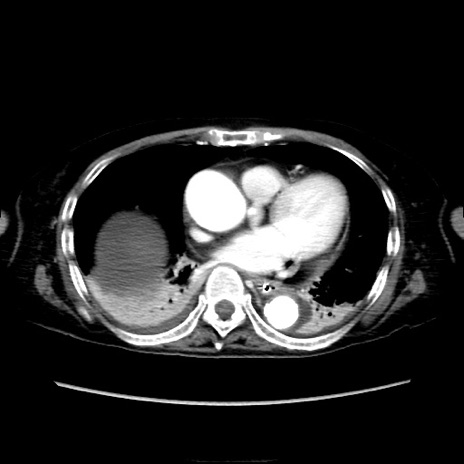

症例40(横断像)

【症例】90歳代女性

【主訴】腹痛・嘔吐

【現病歴】 食欲低下、嘔吐があり昨日他院受診。肺炎と診断され入院となる。入院後より腹部全体に圧痛あり。胃管留置され経過みていたが、症状持続するため、

当院転院となる。

【既往歴】胸椎圧迫骨折、胆石症

【身体所見】腹部:中央に激痛あり、圧痛あり、反跳痛不明

【データ】WBC 17100、CRP 18.82

横断像